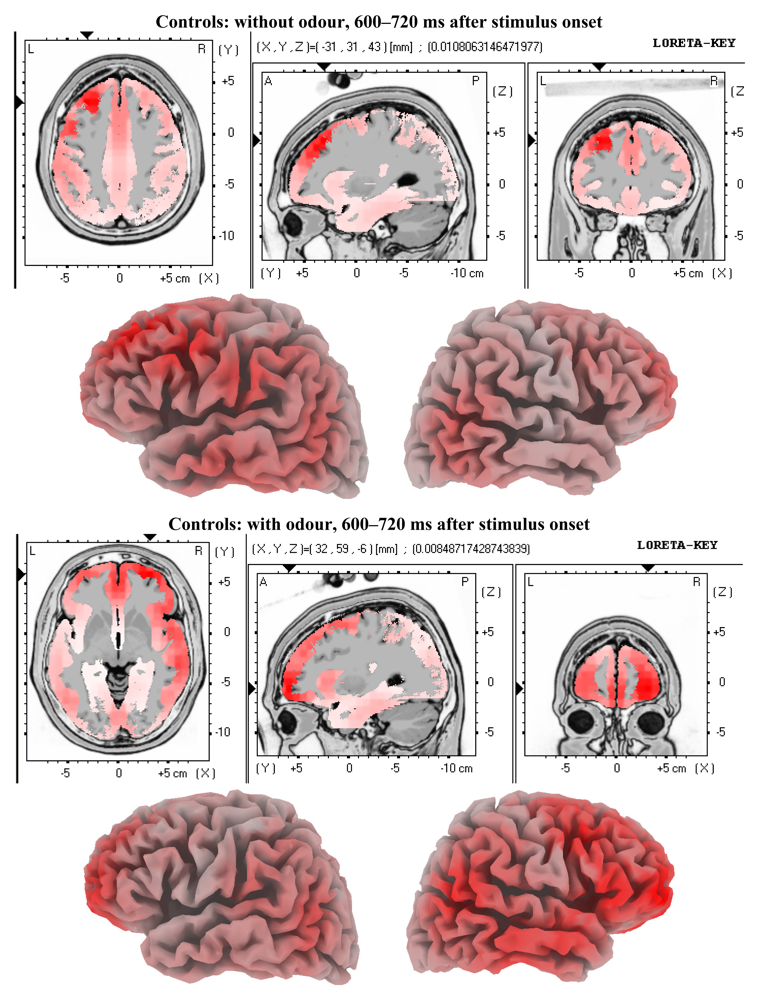

3.2. EEG Data